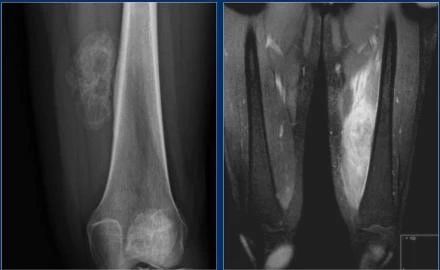

骨梗死典型表现:干骺端或骨干的中央病变,有明确的蛇形边界。可能类似软骨肿瘤。原因:皮质类固醇使用,镰状细胞疾病,创伤,戈谢病,肾移植。骨梗死是指骨干或干骺端的骨坏死,如果骨坏死位于骨骺,则使用缺血坏死一词。下图X线表现为股骨干骺端和胫骨干骺端典型的骨梗死,MR边缘低信号环,压脂可见水肿。

8f175b5edc902c7e31f13ff1c91b8b7b.jpg